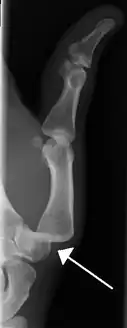

Dislocation of the left index finger

Radiograph of right fifth phalanx bone dislocation

Radiograph of right fifth phalanx dislocation resulting from bicycle accident

Right fifth phalanx dislocation resulting from bicycle accident